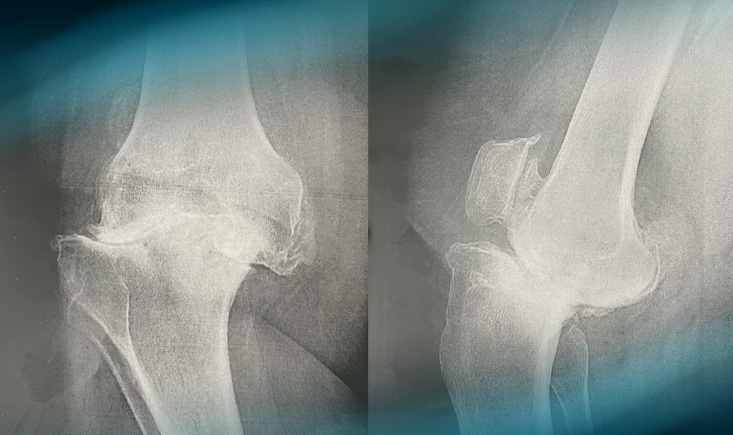

Pre operative planification